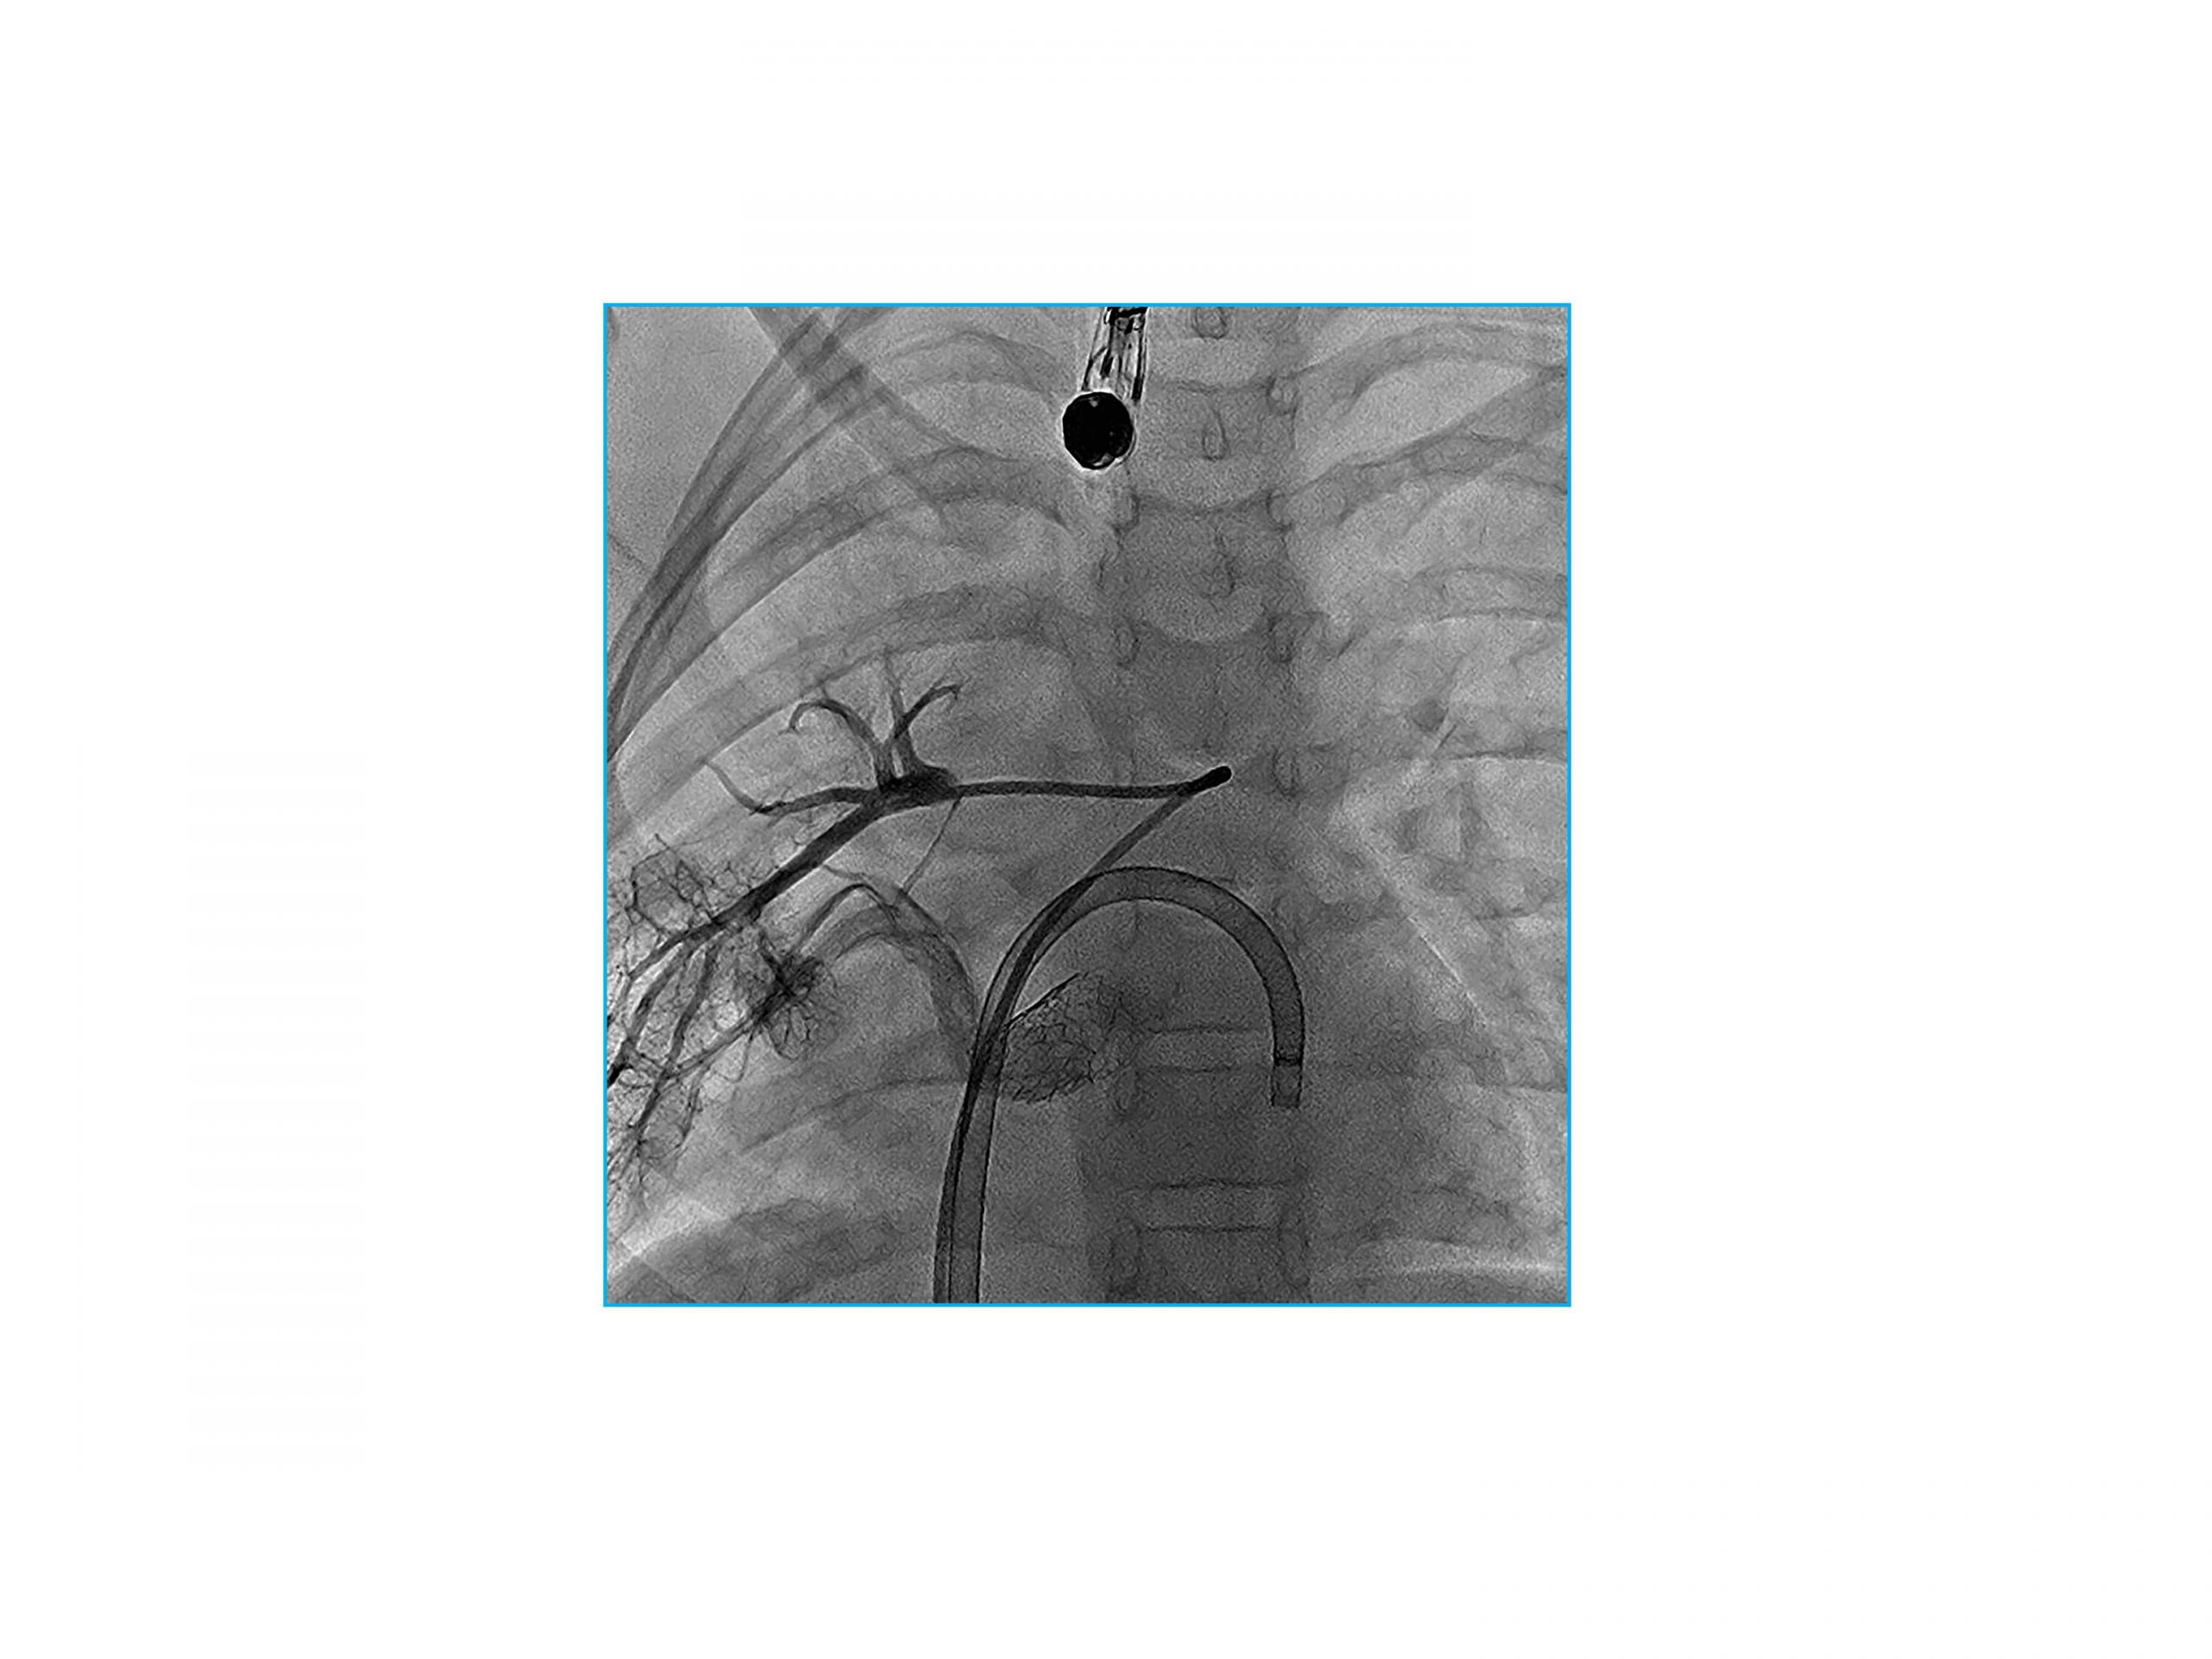

– Right pulmonary capillary wedge angiogram demonstrated the common PV narrowed to 3 mm at the anastomosis site (Figure 3A)

– Stenosis measured 8mm via balloon sizing with a 12mm x 2cm EverCross balloon (Medtronic, Dublin, Ireland) (Figure 3B)